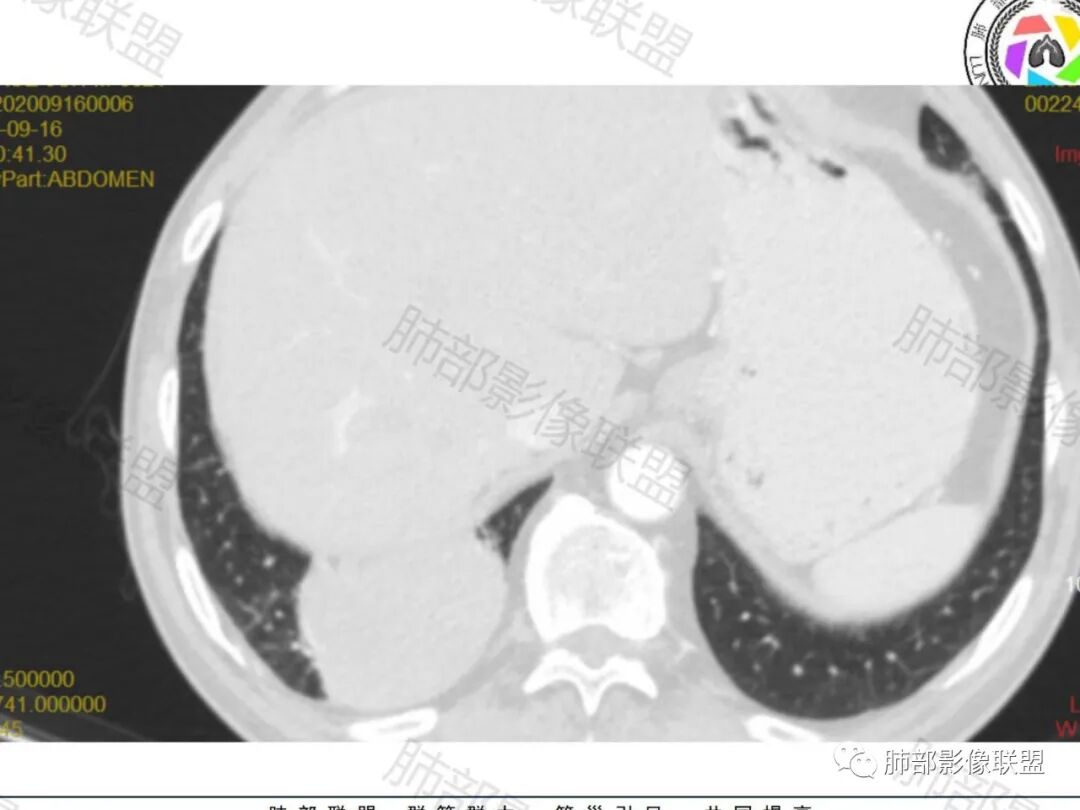

右肺下叶一类圆形肿块影,内缘边缘光滑,外缘边界模糊,可见磨玻璃影,整体以彭隆为主,部分边缘包绕支气管,平扫密度尚均匀,增强后不均匀强化,部分与膈肌黏连,临床,62岁男性,无症状,考虑恶性:腺癌,鳞癌,神经内分泌癌,肉瘤

男性,62,胆结石入院胸部CT偶然发现占位。肿标稍增高,右肺下叶胸膜下肿块,边缘尚清,密度较均匀,增强明显强化,血管贴边,空气新月征?静脉期可见低强化区,首先考虑PSP,鉴别肉瘤样癌及神经内分泌肿瘤

患者中老年男性,检查发现右下肺占位。查肺癌标记物稍有升高。血常规白细胞计数稍降低。胸部CT:右肺下叶后基底段类圆形肿块,边缘光滑,边界清楚,周边见气管受压扩张,增强轻度强化,内见点状低密度影,见血管贴边。综合考虑良性过低度恶性病变,PSP可能,其它恶性肿瘤待排。

老年男性,检查发现右下肺占位。CT:右肺下叶一类圆形肿块影,膨隆,无分叶,边缘基本光滑,近端支气管推挤狭窄,与胸膜夹角为锐角,增强见不均匀强化,未见坏死,近端见血管贴边,胸壁脂肪间隙清楚。考虑良性病变——PSP可能性大。鉴别神经内分泌癌、肉瘤、SFT。

右肺下叶肿块,呈外带大内带小的椭圆形改变(内带受支气管及血管挤压原因),边缘光滑,无分叶毛刺,支气管受压,增强后,均匀延迟强化,动脉期见血管贴边,静脉期内部瘤样血管强化区,相邻胸膜无侵犯,纵隔无淋巴结肿大,符合PSP,不鉴别。

胸部CT:右肺下叶一类圆形肿块影,边界清楚,大部分边缘光滑、外缘边界模糊,邻近支气管推移、血管贴边,病灶内可见分枝状血管,平扫密度尚均匀,增强后大部分均匀延迟强化,部分与膈肌黏连、尾征?考虑:类Ca>PSP>SFT。鉴别肉瘤样Ca,CD等。

肿块位于周围(起自细支气管呼吸道上皮),均匀膨胀生长(符合良性的生长特点),病灶内部大部分密度较均匀,部分小低密度不强化区(囊变),增强强化较明显,边缘血管增粗贴边,临近支气管受压,支持PSP。

含气组织

哦落花时节:

受压推移

南边:

常规肿瘤如果背侧胸膜来源,肿瘤与胸膜之间不应该夹杂含气支气管,会推移

但是肺内可以将支气管外推,夹在胸膜之间

与膈面胸膜类似推断

支持肺内